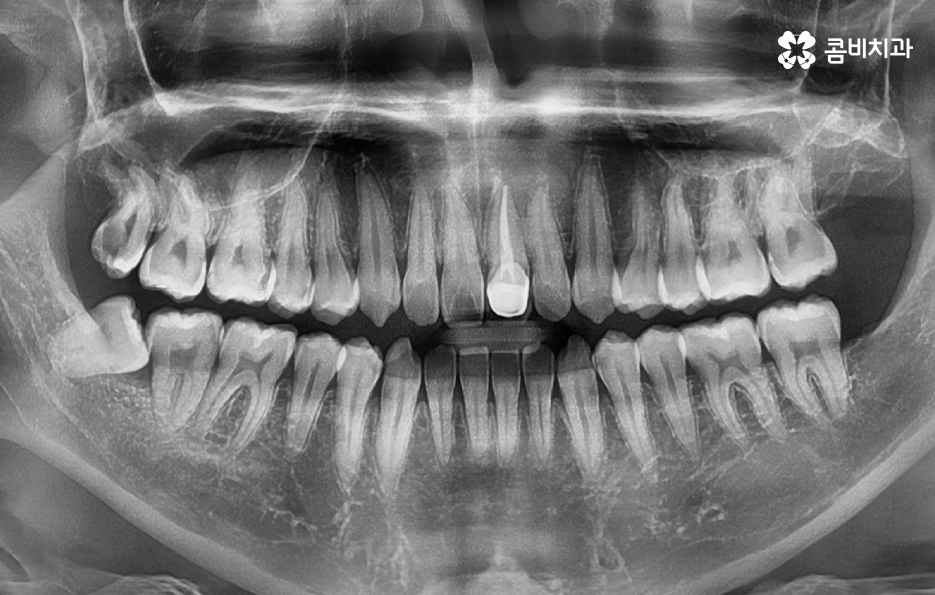

사랑니는 보통 20살 전후에 나기 시작하는데 현대인들은 턱뼈가 점점 좁아지고 있기 때문에 사랑니가 4개 모두 나는 분들도 있지만 1~3개 정도만 나는 경우도 늘고 있고 간혹 아예 안나는 분들도 있어요

사랑니가 자라는 시기에 사랑니가 정상 맹출된 경우에는 청결관리가 잘 되고 있다는 가정하에 꾸준히 검진하고 스케일링을 통해 치석 관리를 하면서 당장 발치를 하지 않아도 되는 경우도 많기 때문에 사랑니라고 해서 무조건 뽑는다고 생각하실 필요는 없겠지만 청결관리가 쉽지 않은 부위이기 때문에 매년 주기적으로 사랑니 상태를 체크해야 할 거예요

사랑니가 자라고 있다는 이유만으로 무조건 뽑아야 하는 것은 아니지만 앞서 설명드린 것처럼 사랑니의 위치가 좋지 않거나 문제가 예상되는 경우에는 사랑니의 뿌리가 깊어지기 전에 20대에 발치하는 것이 보다 유리하다고 할 수 있어요